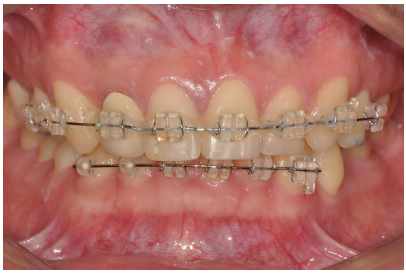

환자: 만 40세 남성

교정 목적: 앞니 배열 개선, 스마일라인 개선

치료 방식: 위·아래 앞니 부분교정

치료 기간: 약 10개월

위·아래 앞니만 교정 장치를 부착

앞니 높이 조절을 통해 최대한 대칭 맞춤

어금니는 기존 상태 유지

치아 배열 개선

위앞니 높이가 가지런해지고, 불규칙하게 배열된 치아가 정리됨

스마일라인 개선

치아 높이 조절만으로도 웃을 때 자연스러운 곡선(Smile Arc) 형성

환자분이 보다 자신 있게 웃을 수 있는 미소 완성